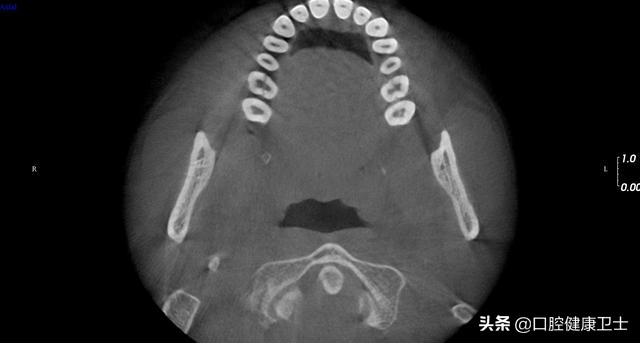

CT见,右上第一磨牙劈裂至髓室底,没有保留可能性,建议拔除。左上第一磨牙,暂不处理。